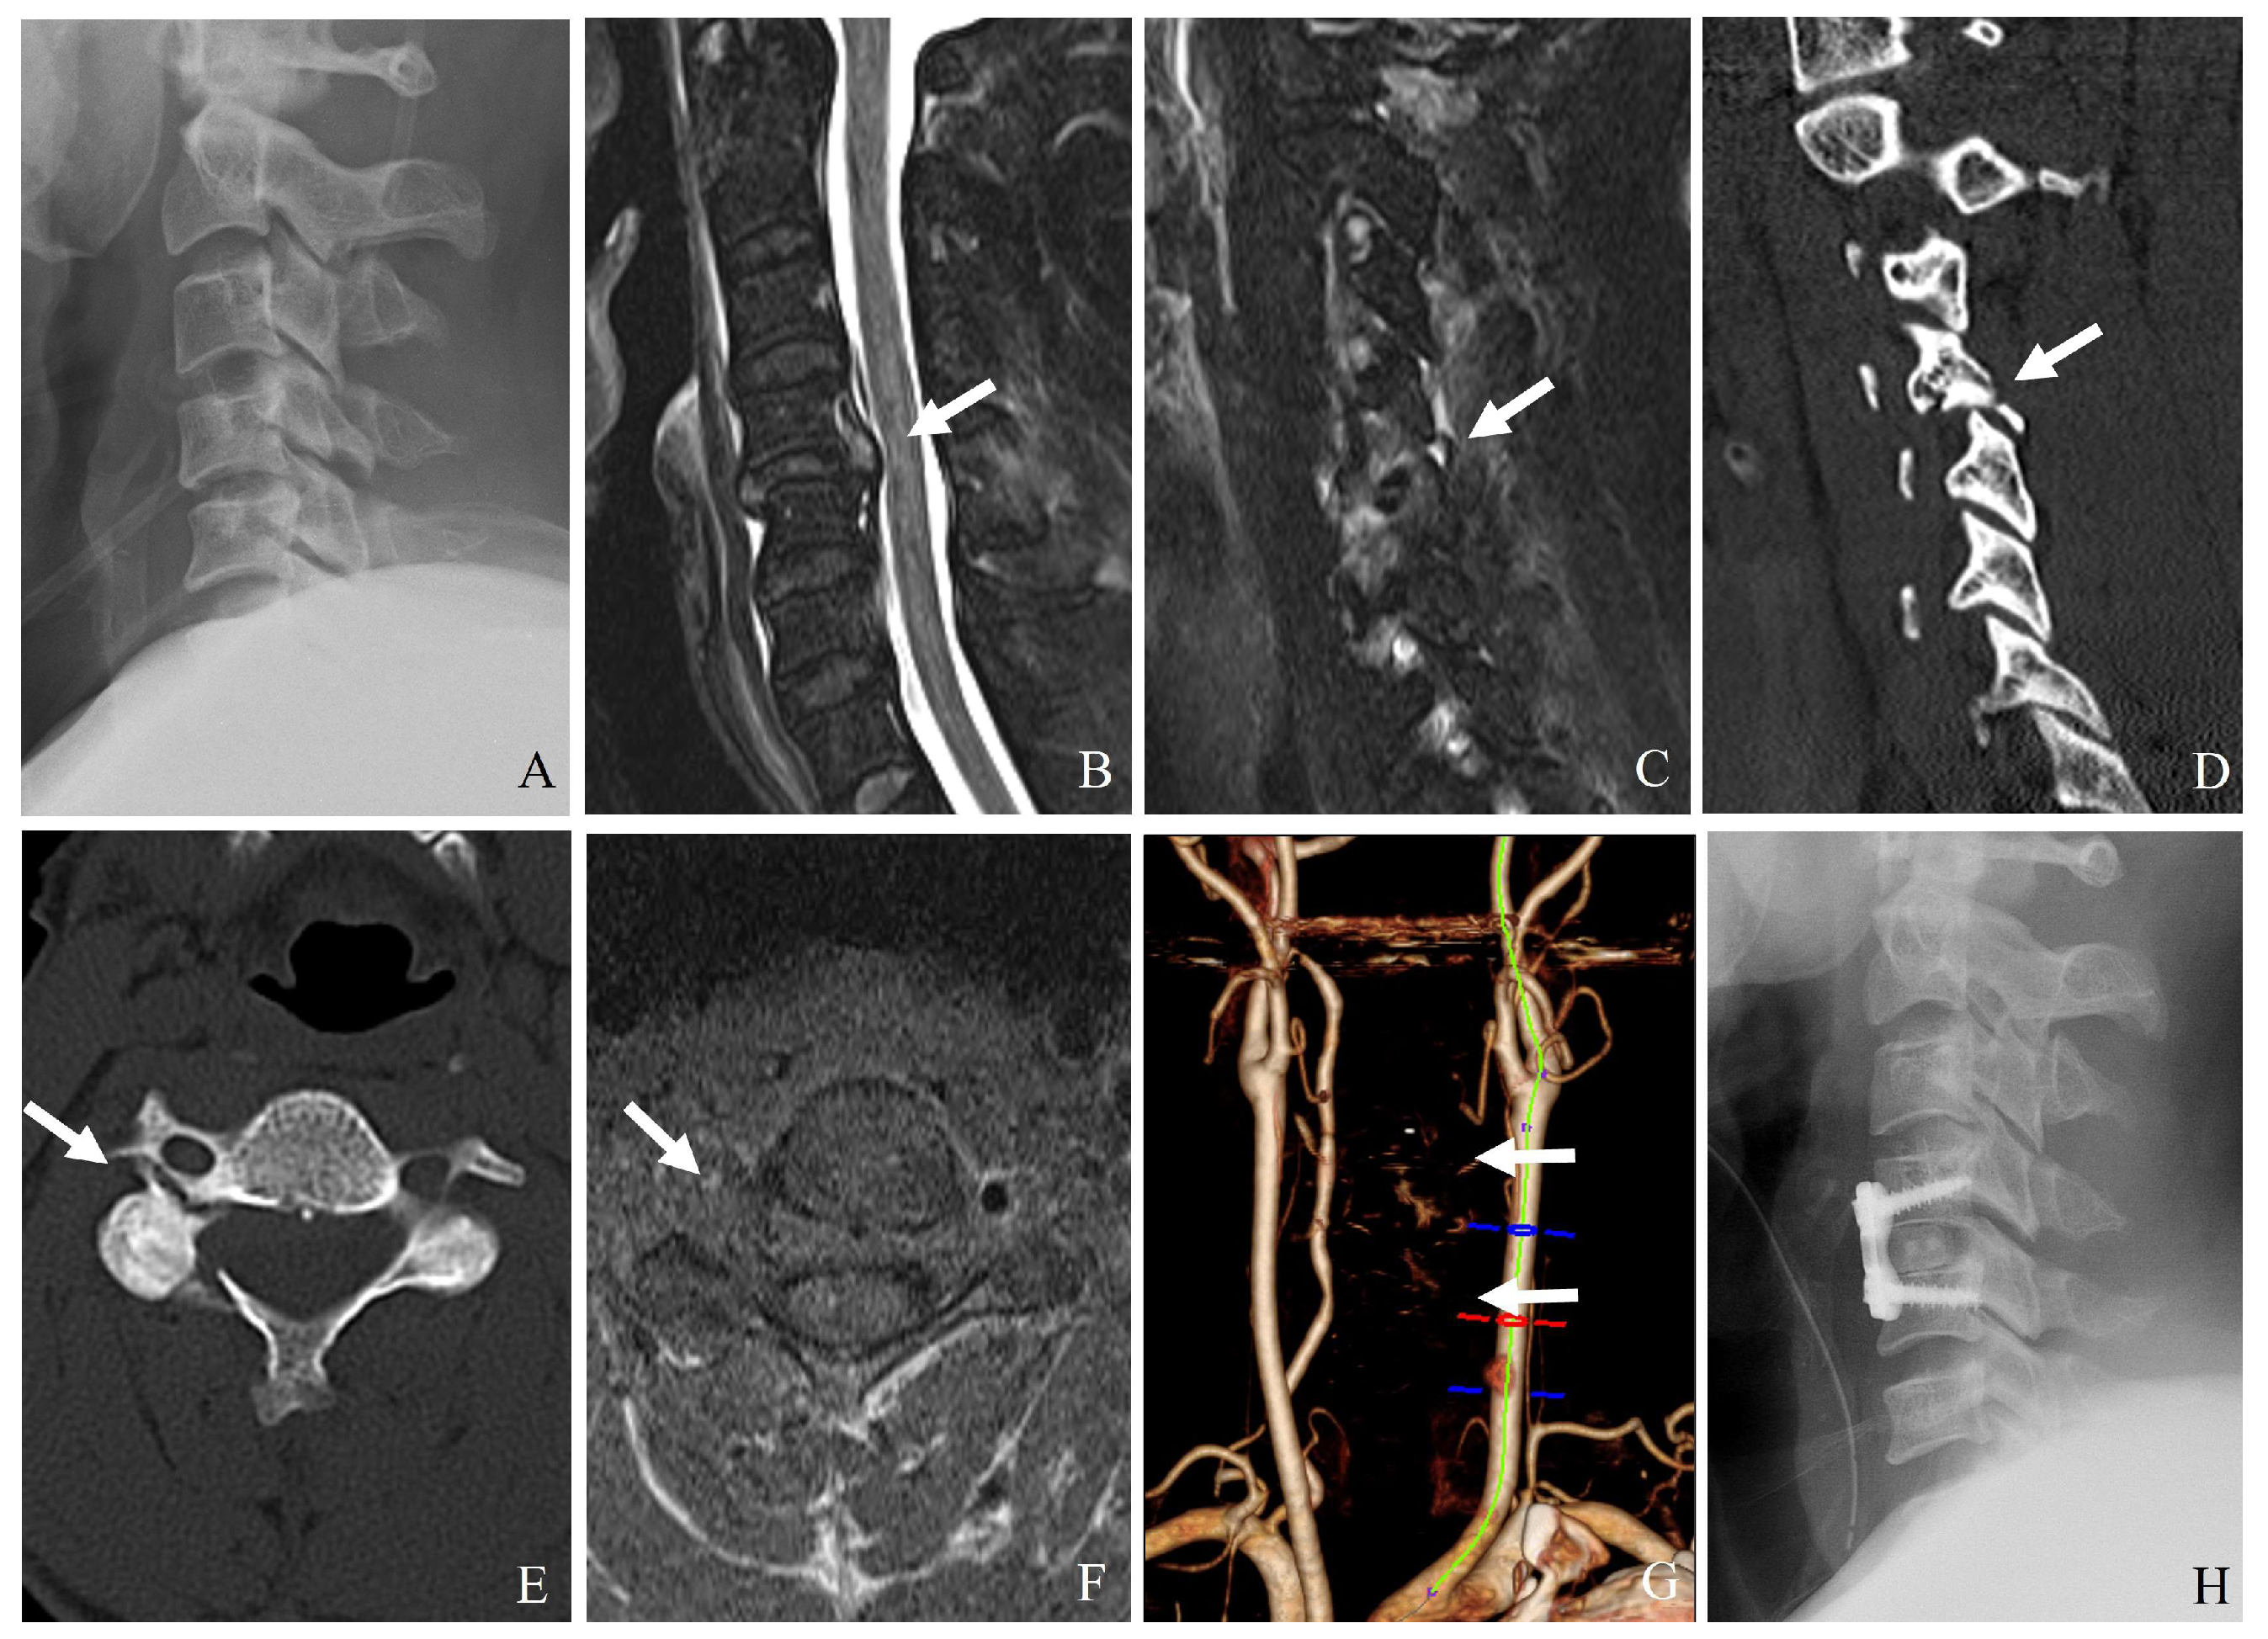

7.2.1. Direct Compression or Stretching

- (1)

- Unilateral or bilateral facet dislocation can cause excessive rotational and translational forces on the vertebral artery, particularly at C3–C6 levels.

- (2)

- Perched or locked facets can lead to excessive stretch or kinking of the artery within the transverse foramen.

- (3)

- Fracture of the lateral mass or pedicle can lead to direct bony impingement on the vertebral artery (Figure 8).

7.2.2. Occlusion from Displacement or Thrombosis

7.2.3. Laceration or Dissection

- A facet fracture extending into the transverse foramen may directly lacerate the vertebral artery.

- High-energy trauma can cause intimal tears, leading to dissection and secondary stenosis or occlusion.

7.3.2. Imaging [13,14,15]

- CT angiography: The gold standard for detecting vertebral artery injuries (Figure 9).

- Magnetic resonance angiography: Useful for assessing arterial dissection and thrombus formation.

- Digital subtraction angiography: The most sensitive but invasive method.